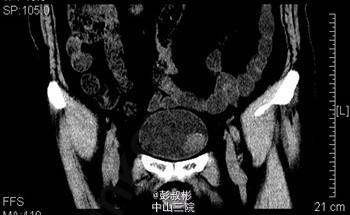

68岁,男性,反复肉眼血尿3个月。盆腔CT:膀胱左前下侧壁约20×21×21 mm肿块,考虑膀胱癌可能性大。术前诊断:膀胱癌。患者合并心肺功能不全,要求保留膀胱。